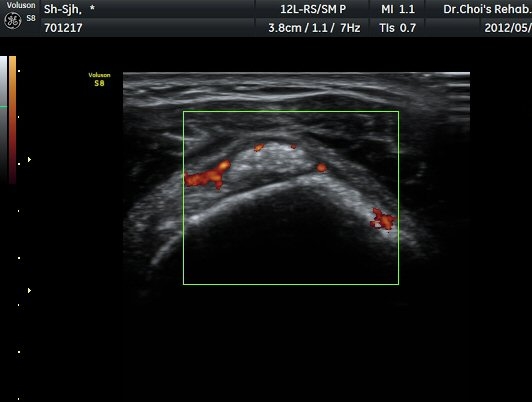

Á߸³»óÅ ¾î±ú ¾Õ Ⱦ´Ü¸é°Ë»ç¿¡¼­ À̺ειڱ٠ÁÖÀ§¿¡ ¼ö¾×Àú·ù°¡ °üÂûµÇ°í(»çÁø 1) ÆÄ¿öµµÇ÷¯

°Ë»ç¿¡¼­ Ç÷·ùÁõ°¡°¡ °üÂûµÈ´Ù(»çÁø 2). À̵ιڱ٠Á¾´Ü¸é°Ë»ç¿¡¼­µµ °Ç ÁÖÀ§ ¼ö¾×Àú·ù°¡ È®ÀÎ